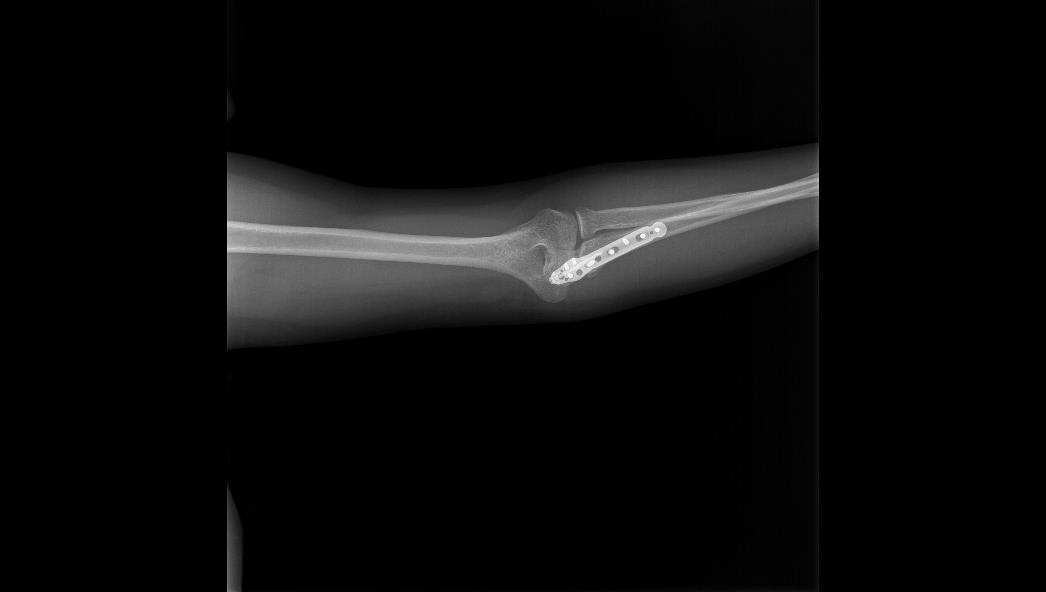

TRUE LOCK Olecranon Anatomic Plates are precontoured for anatomic fit. No need to bend during teh surgery.

Various screws target to help stabilize the coronoid, thereby helping to restore bony and ligamentous struc- tures, which are important for elbow-joint stability.

Long proximal extension and multiple screw options to secure small olecranon fragments to help neutralize the forces of the triceps muscle.